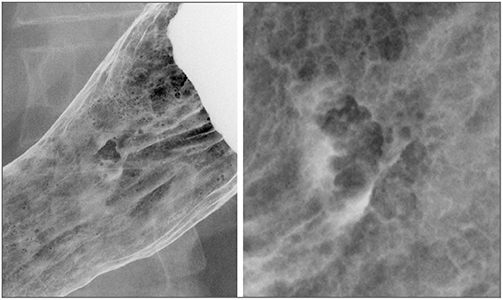

わかりづらいかもしれないので、「形態世界」の作業を以下に表現してみたい。図1は前庭部後壁の大彎寄りにある異常像が現れているX線像である。正面像(図1 左)と側面像(図1 右)とを合わせてその立体形状を想定してみると、30mm大の深い陥凹(潰瘍)を取り巻く丈の高い隆起(周堤)が描出されていることがわかる(正確にはそのように想定したということであり、そう見えない観察者もいるに違いない。たぶん)。つまり、丈の高い隆起の中央に深い陥凹を伴う病変であり、周囲と比べてかなり凹凸が目立つ。図2は、体上部前壁に異常像が現れているX線像である。小さなたまり像の周りに丈の低いはじき像が見られており、これらの所見は丈の低い隆起の中の浅い陥凹を示唆している。

図1 ある異常像(2型の進行型癌)

図2 ある異常像(0−IIc型の表在型癌)